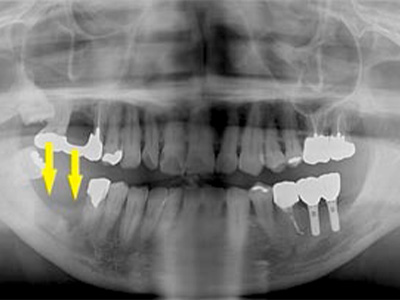

患者様は50代男性。インプラント治療前のレントゲン写真です。

右下顎大臼歯2本の抜歯後のレントゲン写真で、写真の黄色矢印は、歯の周囲の歯槽骨が大きく吸収されてしまっていました(黄色矢印)。 -

CTで見ると、骨吸収の様子が良く分かり、下顎骨の中を通る神経近くまで骨がありませんでした(黄色矢印)。